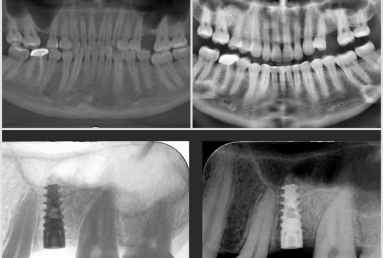

Orthodontic treatment, external sinus lifting.

Orthodontic treatment, external sinus lifting, dental implant and zirconium crown.